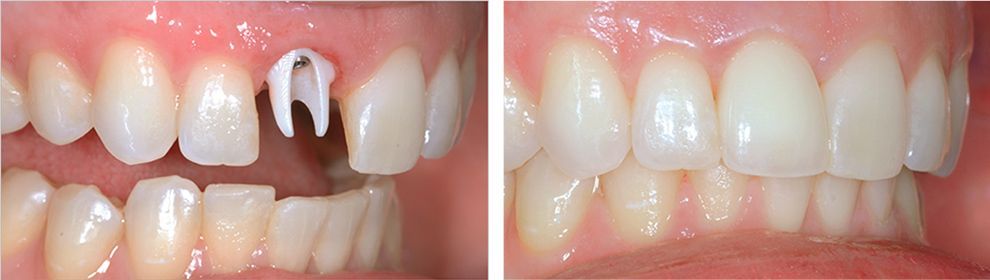

Имплантация с немедленной нагрузкой

За один визит доктор проведёт осмотр, удалит зуб, установит имплантат и временную коронку.

Если вы очень переживаете из-за предстоящего удаления зуба и хотите как можно быстрее его восстановить – вам подойдёт имплантация с немедленной нагрузкой.

Для немедленной имплантации применяют модели с более агрессивной резьбой дающие высокую первичную стабильность.

Вы выйдите из клиники с новым зубом

Удаление зуба и установка имплантата в один визит

Установка временной коронки сразу после имплантации